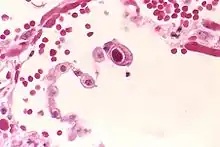

The term owl's eye appearance, also known as owl's eye sign, is used to describe a pattern resembling the shape of a real owl's eye that is found in the study of histology, radiology, and pathology cases. The pattern is used to analyze symptoms in patients within the medical field.

- Owl's eye appearance of inclusion bodies, which is highly specific for cytomegalovirus infection.[2]

- Owl's eye appearance of the entire nucleus – a finding in Reed–Sternberg cells in individuals with Hodgkin's lymphoma.

The owl's eye appearance has a relationship with Reed–Sternberg cells in regards to cytomegalovirus infection.[4] Owl's eye appearance was used as an indication of the presence of the cytomegalovirus for the following case studies.

In a 2000 case study, it was discovered that the owl's eye appearance as a cell body was key for the histopathological understanding of the cytomegalovirus.[2] The study found a strong relationship with a positive CMV PCR (p < 0.001).[2] The discovery led to a result that owl's eye appearances were a strong sign for finding cytomegalovirus inside organs.[2]